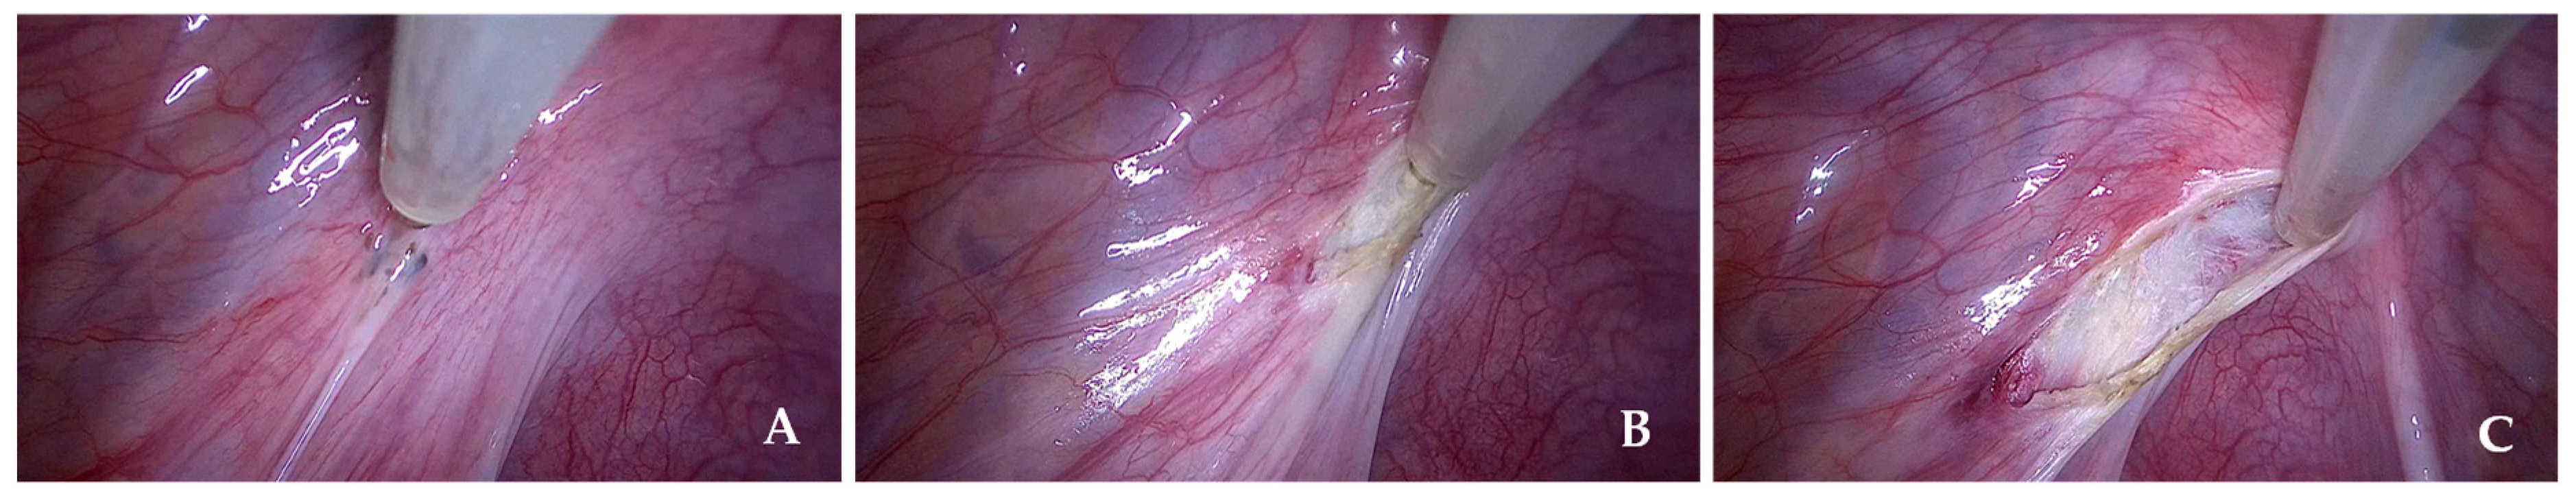

Figure 2 shows a representative intraoperative image of the CUSA from our series.

Figure 2. Representative intraoperative images of CUSA from our series. (A) Pre-procedural view before the start of lesion excision. (B) and (C) Intraoperative views demonstrating tissue fragmentation, irrigation, and aspiration during the use of CUSA.